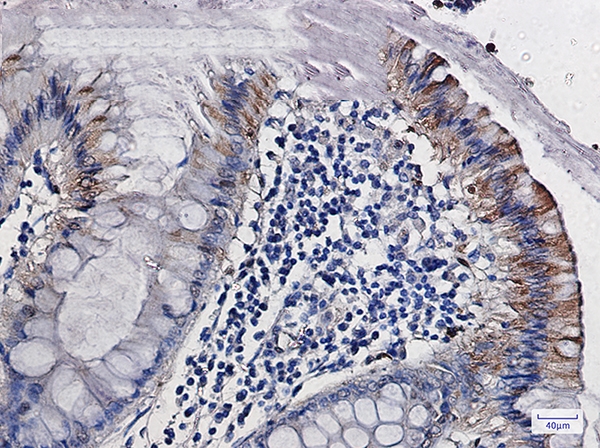

Immunohistochemistry of CDA in paraffin-embedded Human colon cancer tissue using CDA Rabbit mAb at dilution 1/50